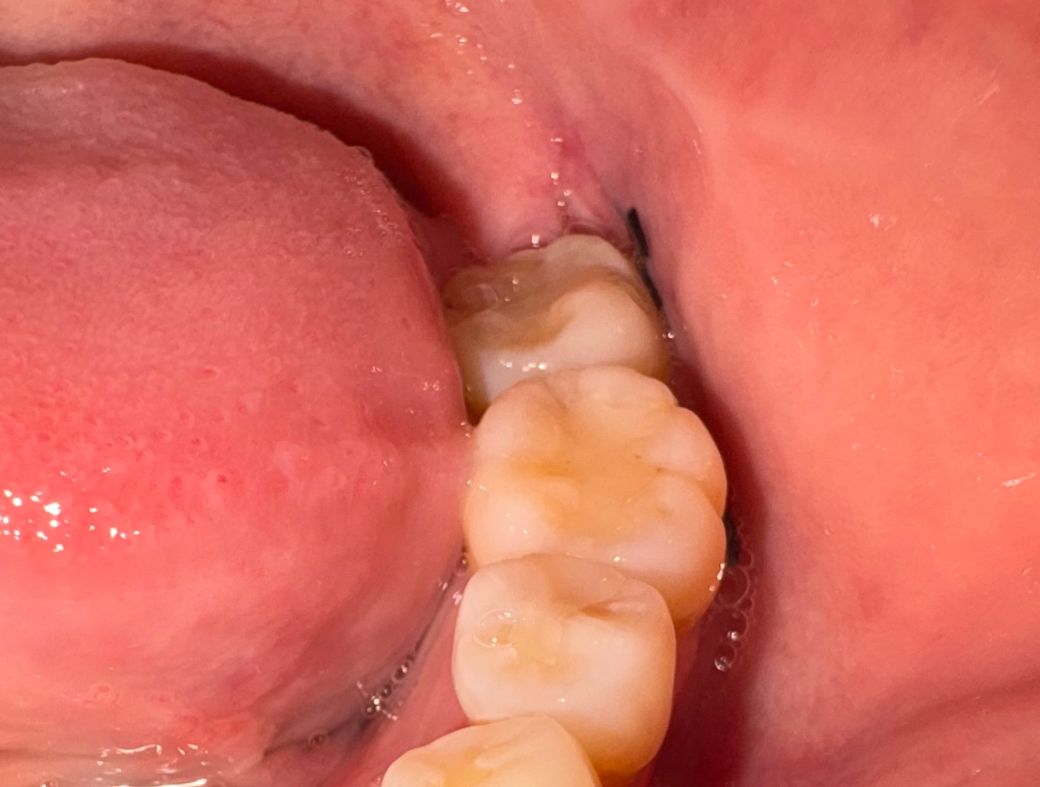

첫번째 사진이 오늘 오전 사진이고 두번째 사진은 같은 날 오후 8시쯤 사진입니다. 저녁에 사랑니 부분을 확인하니 전에 없던 구멍이 생겼습니다..

• 2번 째 사진

실밥이 벌어진건 아니고 잇몸의 붓기가 빠지면서 실밥이 느슨해진거 같습니다. 드라이 소켓은 아닌거 같습니다.

1. 실밥이 벌어진걸까요? 실밥 푸는건 16일에 예약되어있는데 내일 병원에 가는게 좋을까요? -> 식사하고 양치하고 입 벌리다보면 약간 실밥 느슨해지고, 발치공간이 벌어질 수 있습니다, 치과는 원래 약속대로 가세요

2. 드라이소켓일 가능성 있나요? -> 가능성 낮습니다